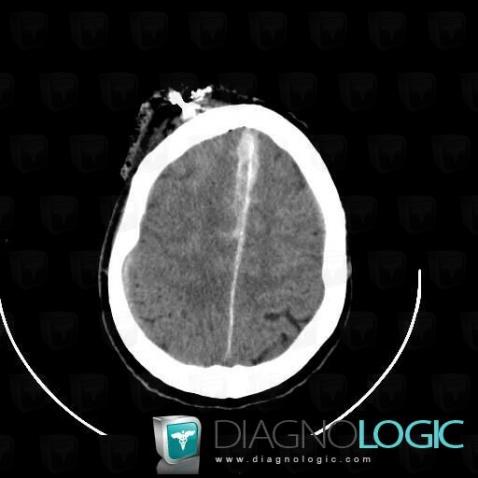

- Diagnosis Subarachnoid hemorrhage, Location(s) Supratentorial peri cerebral spaces, with gamuts Supratentorial extra axial lesionCerebral falx / Midline, with gamuts Increased density of cerebral falx

- Diagnosis Foreign body, Location(s) Cerebral hemispheres, with gamuts Hyperdense intracerebral lesion on noncontrast CT